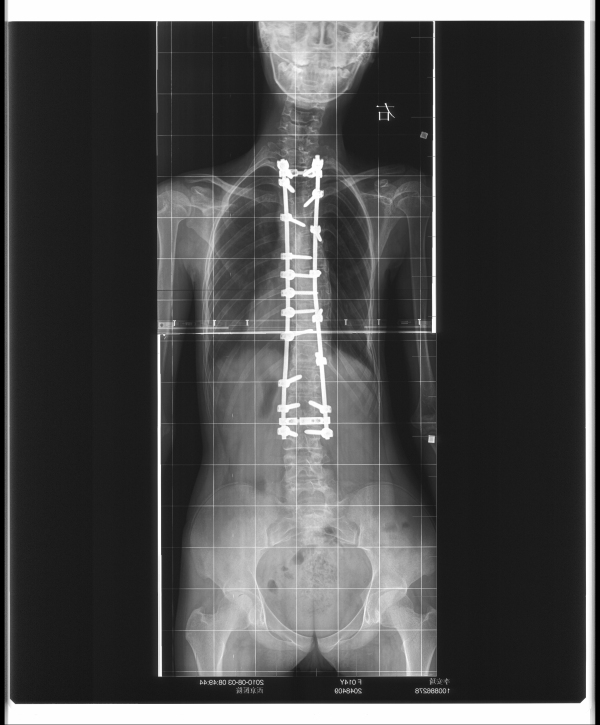

使用平移技术安装内固定系统,X光机下透视,见位置良好,矫形满意。安装横联,冲洗、探查无活动性出血,无异物残留。将取下的棘突剪碎后复合异体骨颗粒植入各关节突部位。

脊柱侧弯术后检查